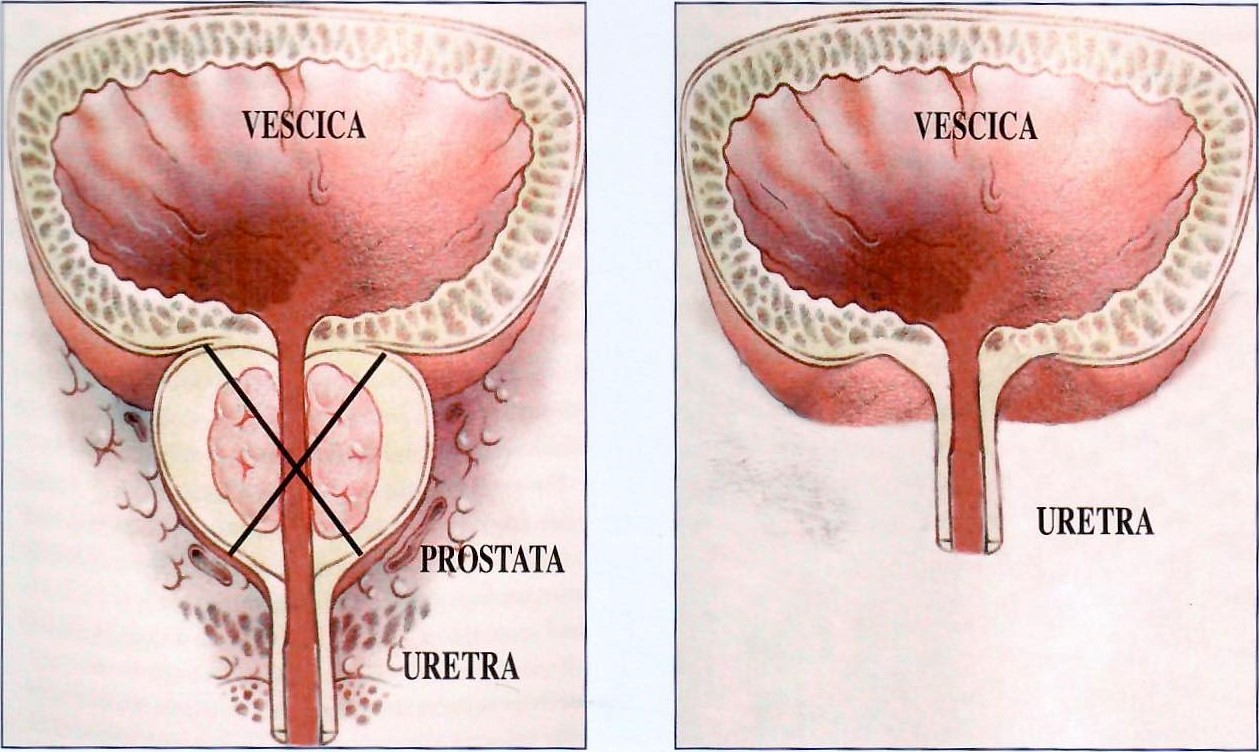

Iperplasia prostatica benigna

PRIMA DOPO